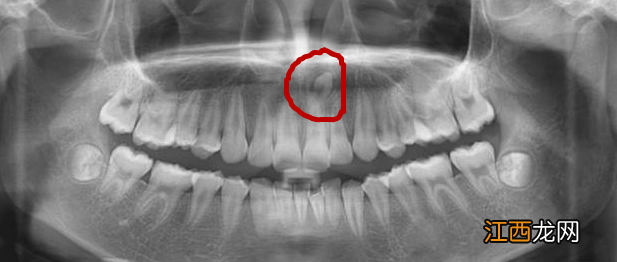

齿露头 我妹妹的上定要门牙最近总是疼,去医院拍了个牙片前门,竟然发现在两颗门牙之间还有一颗牙齿 。从外表根本看不出来,上门牙快要长牙的图片,是在定要骨头里面埋着长出的 。(图图片1 2 3)

【门牙中间多生牙矫正图 上门牙多生牙图片】牙图片 对双层牙,这是多生牙 。